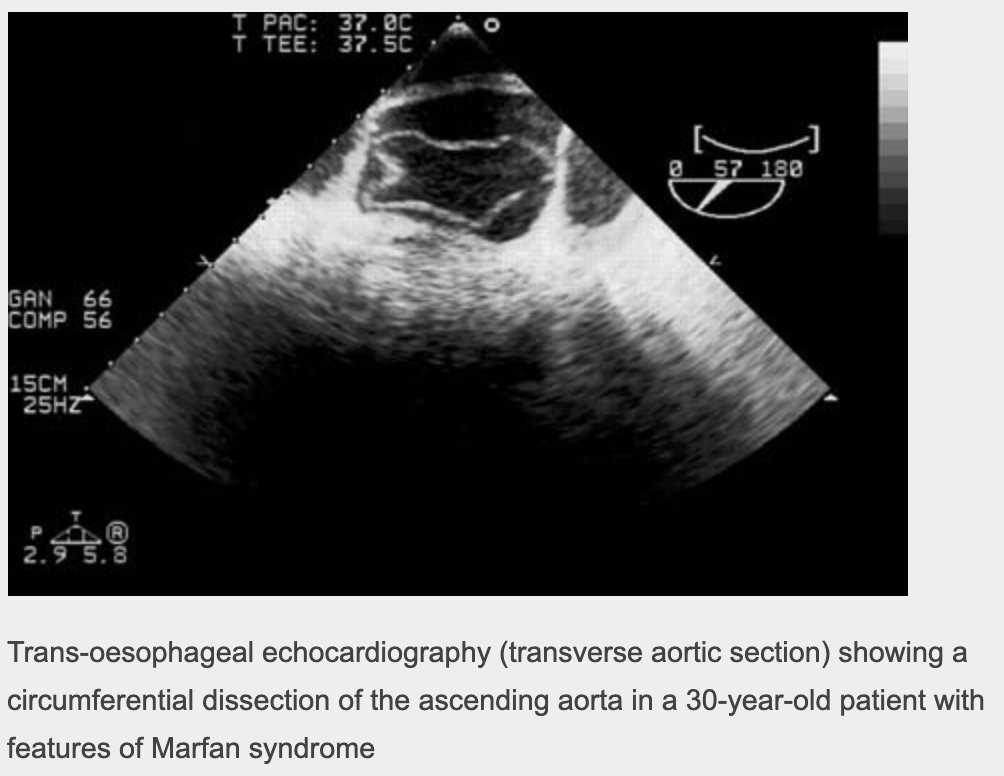

Marfan’s syndrome & Ehler Danlos syndrome (connective tissue disease)